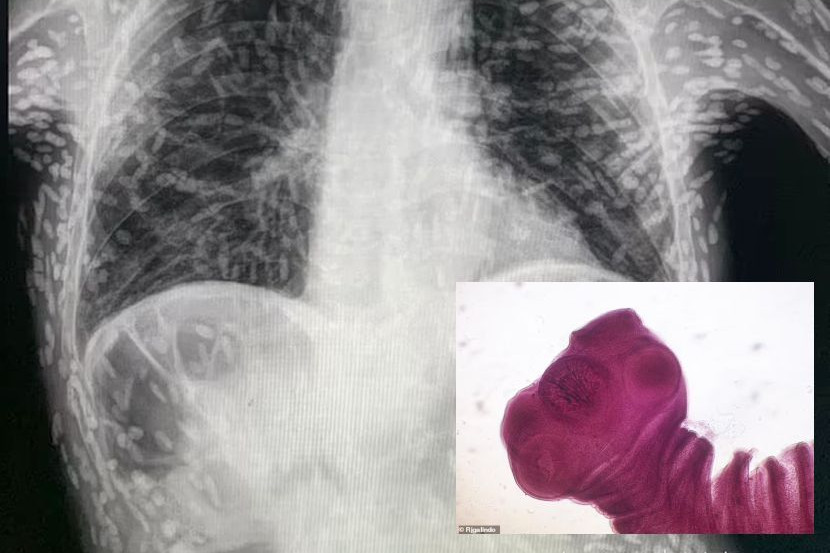

MENGEJUTKAN! Imbasan x-ray badan seorang pesakit yang kononnya mengalami batuk berterusan rupanya dipenuhi sisa berpuluh-puluh larva cacing pita.

Menurut seorang pakar perubatan Brazil, ratusan bintik-bintik terang yang kelihatan pada imbasan tersebut masing-masing mewakili sisa kapur parasit.

Keadaan ini, dipanggil cysticercosis yang mana ia berlaku apabila larva spesies cacing pita yang biasanya hidup di dalam usus, memasuki tisu seperti otot atau otak.

Di situ mereka membentuk nodul keras seperti cyst yang boleh dirasai seperti ketulan di bawah kulit.

Walaupun tidak menyenangkan namun ia secara amnya tidak berbahaya kerana larva tidak dapat hidup manakala cyst yang tinggal boleh menyebabkan masalah lain sekiranya ia berkembang di otak atau mata.